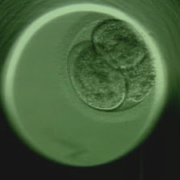

However the new procedure, which uses ‘time-lapse imaging’ to monitor the health of embryos by taking thousands of digital pictures to identify ones that are developing well, could raise the chance of a live birth to 78%, about three times the national average.

The new technique identifies the ‘best embryos’ to be implanted into the womb based on the time it has taken to develop between two key stages in the early life-cycle of the embryo.

Thousands of time-lapse pictures taken during the first few days of an IVF embryo’s life are used to identify the time between the first appearance of the fluid-filled cavity, called the blastula (normally 97 hours), and the full blastocyst (122 hours).

In embryos at high risk of aneuploidy (extra chromosomes) these steps occurred about 6 hours later on average. Aneuploidy is the single biggest cause of IVF failure.

To test the system, the doctors ran the program on time-lapse images of 88 embryos that had been recorded previously for 69 couples at the clinic. Some 61% of the embryos ranked as low risk for abnormal chromosomes led to live births, compared with none of those ranked as high risk.